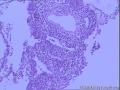

求助胸腺瘤分型

性别年龄31临床诊断

一般病史胸痛胸闷十余天

标本名称纵隔肿物

大体所见穿刺活检条索状组织数条

前12张为胸水涂片,后面为活检穿刺组织

形态支持胸腺瘤B1型,建议染IHC除外结外淋巴瘤的可能

更倾向淋巴瘤。

胸腺瘤不能依靠穿刺小组织分型的,而且确实应该除外淋巴瘤。

感谢各位回复!说一下临床情况:前上纵隔肿物约10cm,发现10余天.CT示肿物界限不清,侵犯心包及一侧胸膜,两所医院诊断胸腺瘤.浅表及肿物周围未见肿大淋巴结.